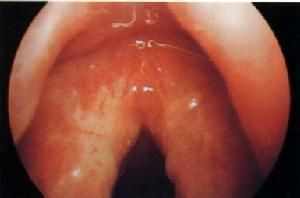

1、慢性單純性喉炎喉黏膜瀰漫性充血、紅腫,聲帶失去原有的珠白色,呈粉紅色,邊緣變鈍。黏膜表面可見有稠厚粘液,常在聲門間連成粘液絲。

2、肥厚性喉炎喉黏膜肥厚,以杓間區較明顯。聲帶也肥厚,不能向中線靠緊而閉合不良。室帶常肥厚而遮蓋部分聲帶。杓狀會厭襞亦可增厚。

3、萎縮性喉炎喉黏膜乾燥、變薄而發亮。杓間區、聲門下常有黃綠色或黑褐色乾痂,如將痂皮咳清,可見黏膜表面有少量滲血。聲帶變薄,其張力減弱。

喉炎(1)慢性單純性喉炎可見喉黏膜瀰漫性充血,聲帶失去正常光澤,呈淺紅或暗紅色,也可在其卜看到舒張的血管紋,聲帶邊緣增厚,喉腔常有分泌物附著。

(2)肥厚性喉炎可見喉黏膜呈暗紅色,聲帶增厚,室帶明顯增厚,甚至在發音時可以遮蓋室帶,喉腔內可見有分泌物附著。

(3)結節性喉炎可見在兩側聲帶前、中1/3交界處的邊緣有對稱的小結突起,色白,如粟米大小,基部略紅,發聲時兩聲帶不能緊密閉合。